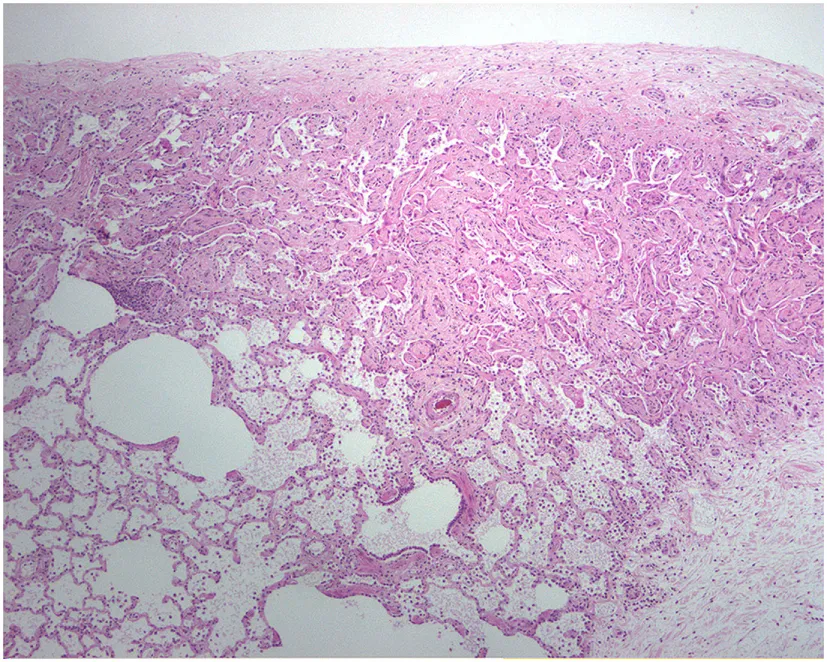

A study on Westies (109) found that the majority of dogs with IPF showed multifocal areas of accentuated subpleural and peribronchiolar fibrosis with occasional “honeycombing” and profound alveolar epithelial changes, reminiscent of human UIP and not commonly seen in NSIP. Interstitial fibroblastic foci, characteristic of UIP, were not seen in WHWTs with IPF. Progressive fibrosis, with intra-alveolar organizing fibrosis alongside interstitial mature collagen deposition, was present within the more severely affected areas of lung in WHWTs with IPF. Severe pulmonary lesions were seen more commonly in the caudal than in the cranial lung lobes.

The ubiquitous gammaherpesvirus equine herpesvirus 5 (EHV 5) has been detected in lung tissue from horses that develop progressive pulmonary fibrosis and is now considered to be the likely cause of this disease in these animals (111). The pathology of this disease is distinct from human IPF, demonstrating multiple nodules and is therefore termed equine multinodular pulmonary fibrosis (111). Although the pathology is not the same as IPF, there are striking overlapping features including weight loss and gradual exercise intolerance, accompanied by characteristic radiologic features (111). Temporal heterogeneity or fibroblast foci, hallmarks of human disease, are not present in the disease in horses, though these characteristics have been described in feline pulmonary fibrosis (111, 112). Similar to EBV in humans, which has been associated with IPF, EHV 5 is a ubiquitous subclinical gammaherpesviral infection in horses (113). Considered largely non-pathogenic in the natural host, some strains of EHV5 appear to be pathogenic and capable of inducing lung fibrosis (103). While EHV5 was isolated from horses with spontaneous disease, the virus was not isolated from dead inoculated horses that developed lung fibrosis (111). This model raises interesting questions regarding induction of lung fibrosis by EHV 5 during viral latency versus lytic infection.

The authors acknowledge the Lester and Sue Smith Foundation, Coalition for Pulmonary Fibrosis, and the Pulmonary Fibrosis Foundation for their support. The authors also acknowledge Amy Miele, BVM&S MRCVS (University of Edinburgh) for her contributions in providing veterinary histopathology images used in the construction of Table 1. AT is a recipient of a Marie Curie/Sklodowska ERS/RESPIRE 2 fellowship (8860-2015). All authors have no financial affiliations or conflicts of interest to disclose.